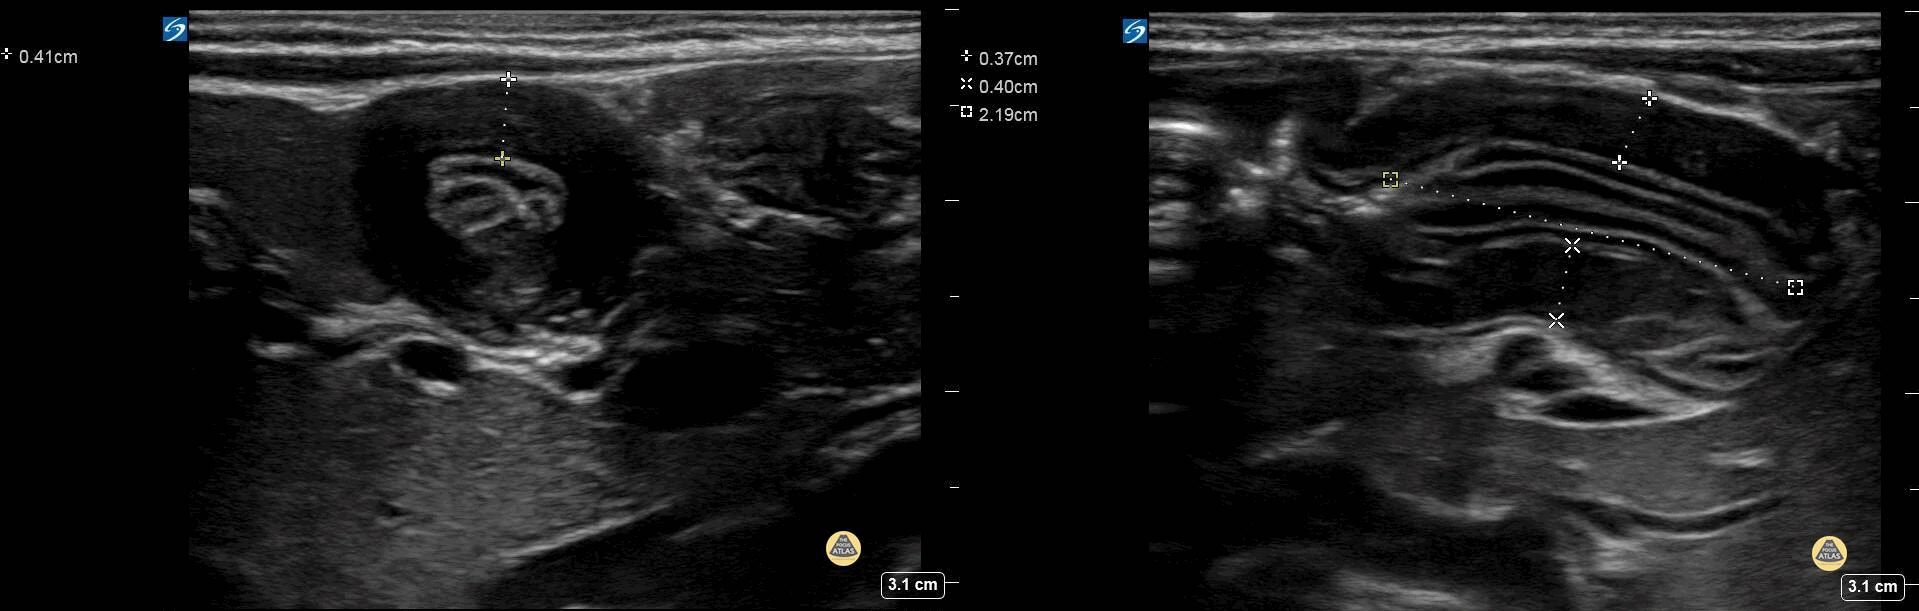

Peds-Gastrointestinal - Pyloric Stenosis 2 (2/2)

2+ weeks projectile vomiting. Extreme lab abnormalities including Cl 67. CG4: 7.57/67/34/60, base excess >30, lactate 3.23. The pyloric channel is elongated, thickened, and has an absence of trans-pyloric flow. Contributor: Matthew Moake, MD PhD